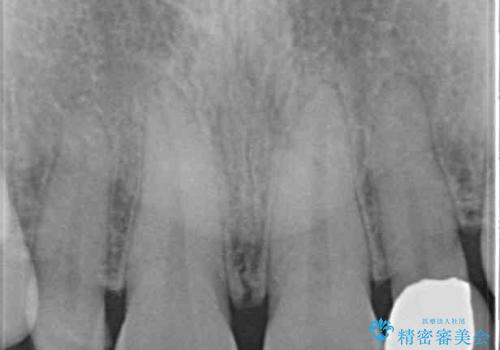

- 前歯の矮小歯に貼り付けられていたラミネートベニアが外れてしまったとのことで来院された患者様です。

反対側の矮小歯は裏打ちが金属であったため、両方の歯ともにオールセラミッククラウンにて補綴することとしました。